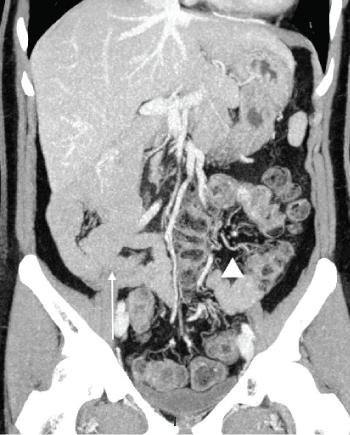

Figure 4: Contrast enhanced CT: Intestinal malrotation Maximum Intensity Projection coronal reconstruction showing anomalous disposition of the entire small bowel and colon, with small bowel located on the right side of the abdomen (arrow), while colon is on the left side (arrowhead). View Figure 4